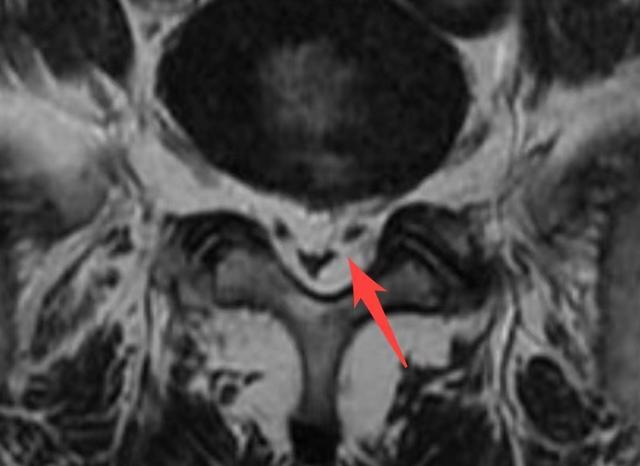

入院后的CT结果显示“椎间盘略有膨出”,这一结果难以解释他如此明显的不适症状。于是,在盛斌主任的建议下做了腰椎核磁共振,结果仍然显示:腰椎间盘轻微膨出,神经压迫不明显。为了找到导致患者症状如此严重的根源,盛斌主任反复仔细查阅影像资料后发现,其腰椎管内有异常增生的脂肪信号,初步判断为少见的“椎管内硬膜外脂肪增多症”。

▲术前MRI显示:椎管内有异常增多的脂肪信号

“该病发病率仅为2.5%~25%,好发于肥胖人群,男性更为多见。”盛斌主任解释,正常人的椎管内都含有少量的脂肪组织,如果脂肪含量异常增多,对脊髓和神经产生明显压迫,就会出现相应的神经压迫症状。当脂肪增多位于脊髓胸段水平时,最常见的症状为进行性背痛;当发生于脊髓腰骶段水平时,可出现髋部、下肢缓慢进行性无力,多发神经根病,麻木、感觉异常,间歇性跛行,大小便失禁,共济失调等症状。